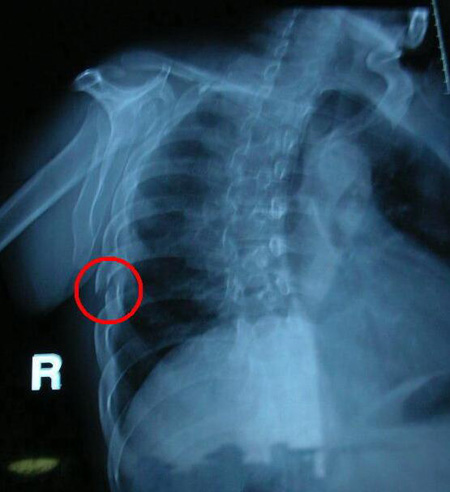

首先X线检查是一个多重组织的投影检查,在胸片上显示的图像有重叠干扰。再加之肋骨的立体形态投影到胸片上时腋侧肋骨组织重叠,结构显示欠佳。肩胛骨,锁骨骨折及肋骨影像重叠时容易掩盖肋骨骨折。后肋靠近胸椎及前肋软骨部分都容易漏诊。膈下肋骨密度对比差,也容易漏诊。

其次检查体位选择不当也是引起漏诊的原因之一。如果胸部外伤患者只开了胸部正侧位检查,肋骨骨折在一个独立胸部正位片上是很难看清的,特别是腋侧肋骨骨折极易漏诊,而侧位是根本无法观察肋骨的。

肯定的回答:胸部正双斜位,是观察肋骨骨折的最佳体位。因为双斜位可以将腋侧肋骨骨质结构展示的更加完全。然而,并不是只要拍摄胸部正双斜位就能保证肋骨骨折不被漏诊,因为只要肋骨骨折对位对线良好,无明显的分离移位,再加上肺纹理的重叠也是极易被漏诊的。只有经过一段时间,随着呼吸运动,肋骨骨折的部位会较之前有所移位,或者骨折部位产生骨痂,才能被发现,所以也就有了报告单上“建议隔期复查”的字眼了。

除了做X线检查,有时还需要做CT检查,CT的横向断层扫描可以减少组织的重叠,暴露骨折的部位。但CT也有检查的局限性,因为是断层扫描就存在图像的不连续性,也会导致肋骨骨折的漏诊。